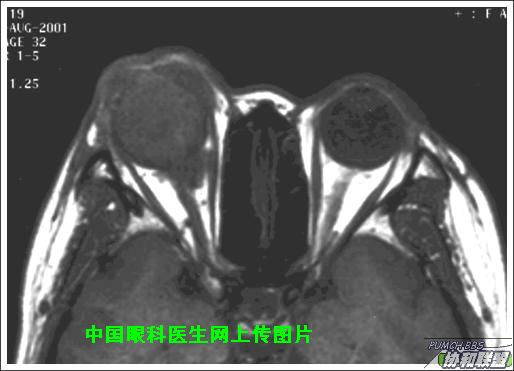

出院后半年发现右眼出现肿物,增长较快,随来京再次就诊(图1),转来我科。门诊检查发现:右眼无光感,结膜下肿物,突出睑裂。眼球突出,上移位。眶外侧可触及硬性肿物。超声(图2),CT(图3),MRI(图456)显示如图.

此主题相关图片如下:

图片点击可在新窗口打开查看